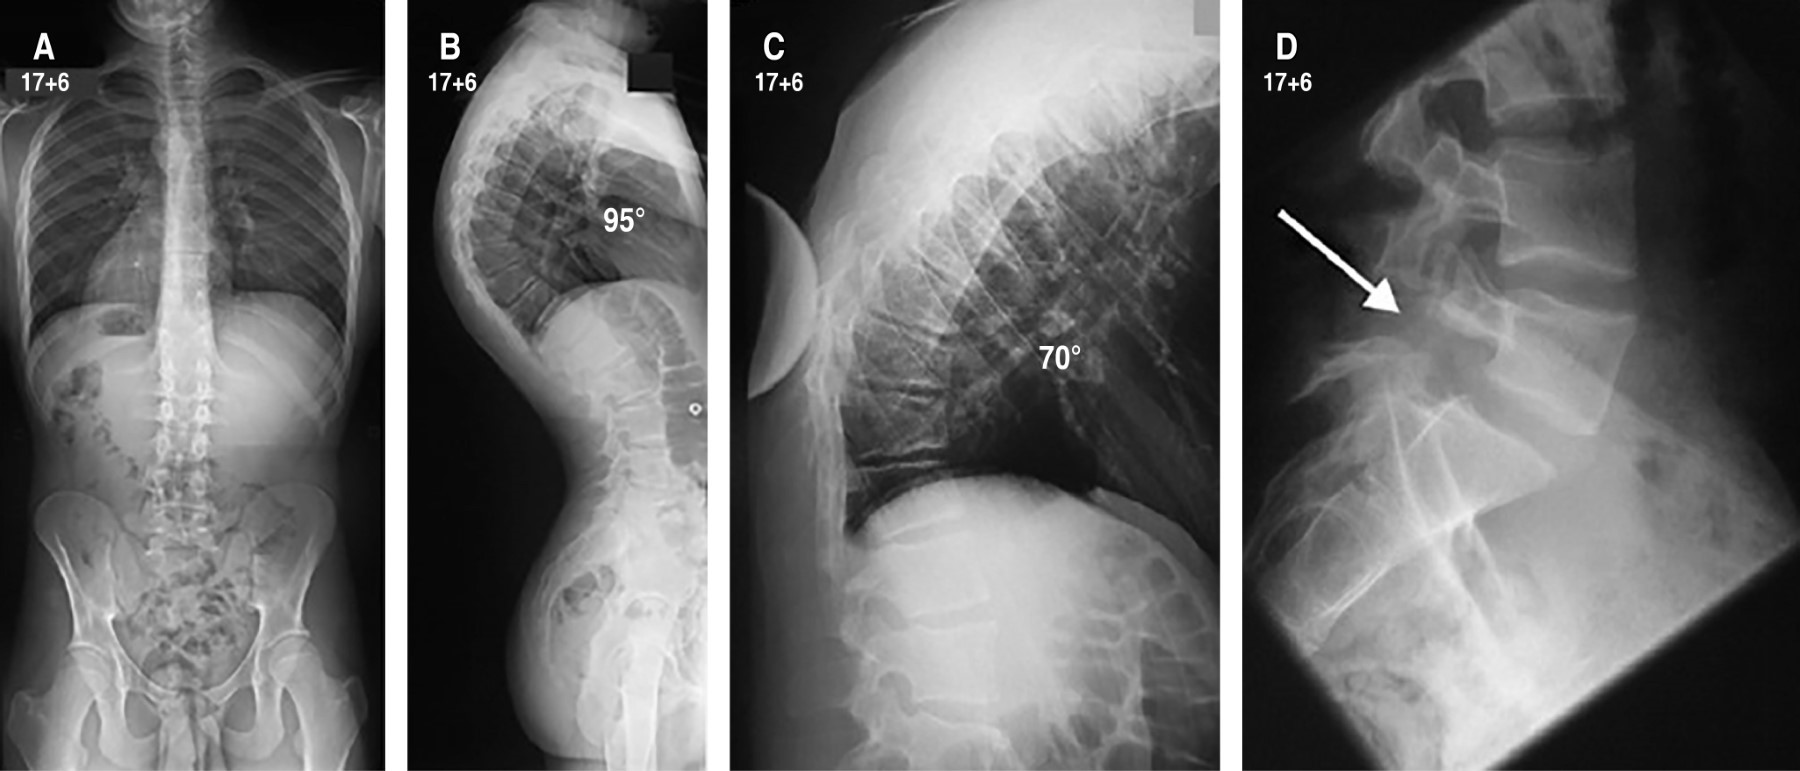

Debe realizarse una radiografía de columna en proyección lateral con el paciente de pie y con los hombros y brazos en 90°, o sobre la clavícula ipsilateral (en posición clavicular). Para la medición del ángulo de cifosis, se seleccionan las vértebras finales craneal y caudal incluidas en la deformidad. La medida del grado de acuñamiento se obtiene del ángulo de intersección de las tangentes sobre los platillos superior e inferior de cada cuerpo vertebral.9 El criterio diagnóstico establece un acuñamiento superior a los 5° en al menos tres vertebras consecutivas en el ápex de la cifosis (Figura 2).1 También son hallazgos comunes en la radiología la presencia de nódulos de Schmorl, la irregularidad y el adelgazamiento de los platillos vertebrales y el pinzamiento del espacio discal. Para la medición del grado de flexibilidad de la hipercifosis se emplea la proyección lateral con el paciente en hiperextensión sobre una cuña o pivote (Figura 3).1 En la enfermedad clásica tipo I, el ápex de la cifosis se localiza entre T6 y T9. En el tipo II, el ápex de la cifosis se localiza sobre la charnela toracolumbar.10

Tratamiento quirúrgico. La principal indicación para el tratamiento quirúrgico es deformidad cifótica dolorosa que no responde al tratamiento conservador, deformidad cosméticamente desagradable, curva funcionalmente progresiva o déficit neurológico/compresión de la médula espinal. Tradicionalmente, se ha ofrecido cirugía cuando la magnitud de la curva supera los 65-80° grados, especialmente en adultos. Las indicaciones cardiopulmonares para la intervención quirúrgica son raras y aparecen únicamente en pacientes con curvas > 100°. En el contexto de la deformidad progresiva, es probable que los pacientes mayores tengan una curvatura más severa y menos flexible que sólo se pueda corregir quirúrgicamente.16